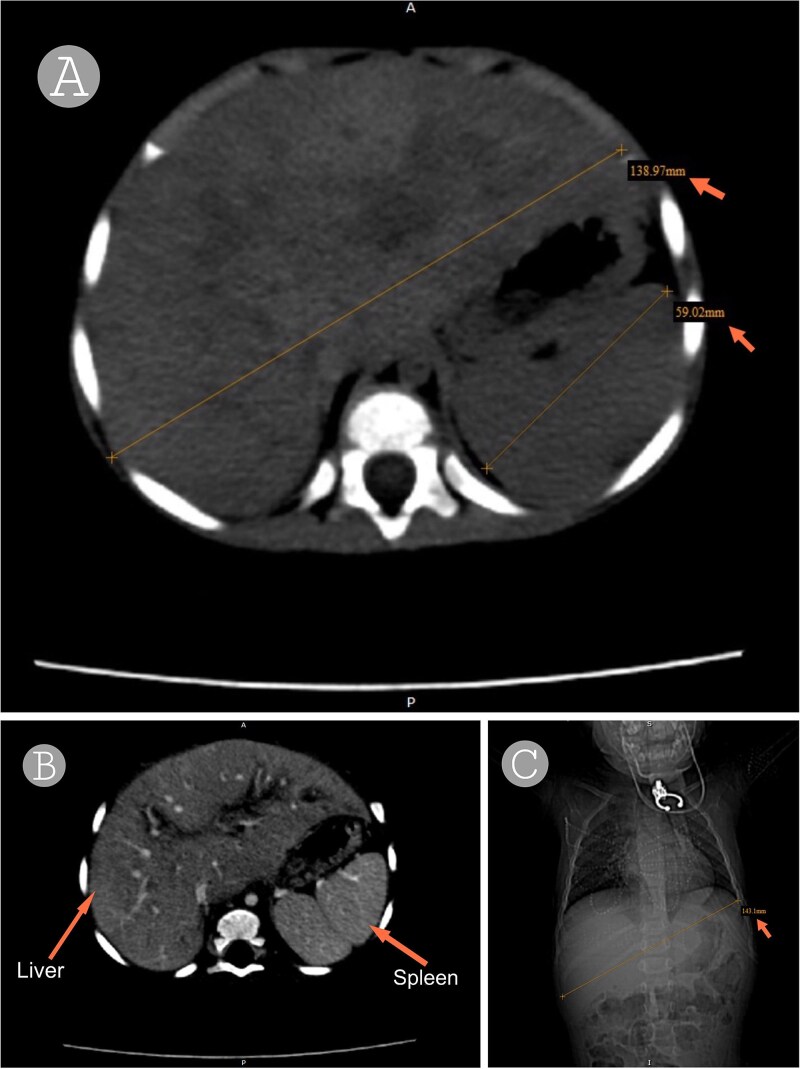

Sneddon syndrome (SS) is a rare neurocutaneous disorder consisting of livedo racemosa (LR) and cerebrovascular disease with an incidence of 4 per 1 000 000 annually. It may be idiopathic or associated with autoimmune or genetic factors, including deficiency of adenosine deaminase 2 (DADA2). We describe a 17-month-old girl with recurrent fevers, hepatosplenomegaly, LR, and progressive liver fibrosis. A pathogenic ADA2 mutation and LDLR mutation associated with familial hypercholesterolemia (FH) were detected by genetic testing. Despite corticosteroids, etanercept, and immunosuppressants, she continued to deteriorate and developed portal vein thrombosis and increasing hepatic dysfunction. DADA2 is well described to cause systemic vasculopathy, but its association with liver fibrosis is still unclear. Our case highlights a potential association between DADA2 and LDLR mutation leading to hepatic injury, extending the broad spectrum of SS-related complications. Further research is needed to understand the role of these genes and their mutations in the systemic and hepatic manifestations of SS.